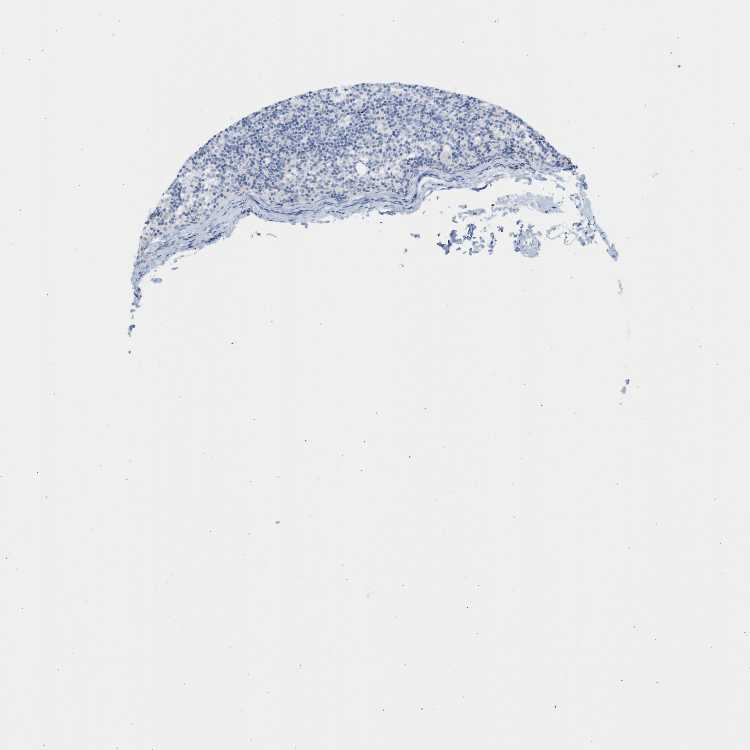

TISSUE PRIMARY DATA LYMPH NODE Show tissue menu

Lymph node

LYMPH NODE - Antibody stainingi

Antibody staining in the annotated cell types in the current human tissue is reported as not detected, low, medium, or high, based on conventional immunohistochemistry profiling in selected tissues. This score is based on the combination of the staining intensity and fraction of stained cells.

Each image is clickable and will lead to virtual microscopy that enables deeper exploration of all samples and also displays staining intensity scores, fraction scores and subcellular localization as well as patient and tissue information for each sample.

Antibody HPA001667Antibody CAB016724

Germinal center cells Not detectedNot detected

Non-germinal center cells MediumNot detected